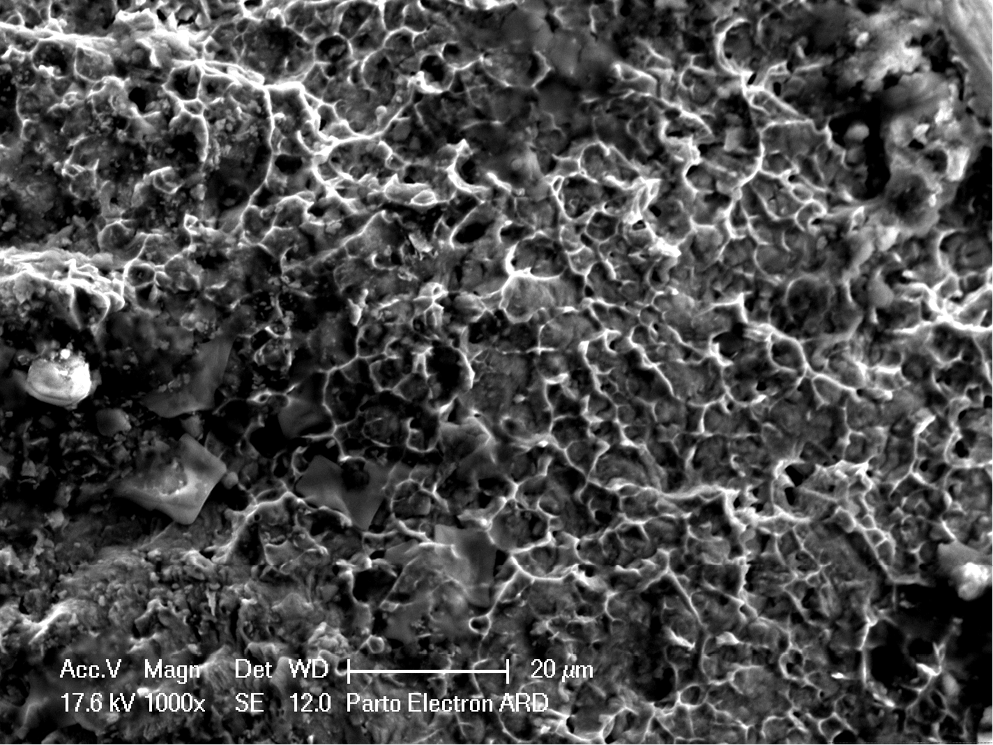

For the cyclic fatigue test, a stainless-steel metal block with a simulated canal with a curvature angle of 60°, a curvature radius of 5 mm and a length of 25 mm was used (Figure 1). It was designed in such a way so that the file could move freely within the canal. The file was inserted into a handpiece connected to an endodontic motor (Silver; VDW, Munich, Germany). The block and handpiece were fixed in place with a clamp. The engine speed was set at 300 rpm and a torque of 5.1 N∙cm, based on the manufacturer’s recommendations. Before starting the procedure, oil was poured into the canal to reduce friction. The file was inserted into the canal up to a length of 25 mm. The block was fixed inside a recipient that was filled with 5.25% sodium hypochlorite. The temperature was preset at 22°C, 4°C and 37°C with a tolerance limit of 1°C. Time was measured with a timer, starting from the moment when the file began to rotate. The timer was stopped a fracture was observed or after hearing a fracture sound, and the time was recorded. The time in minutes was multiplied by 300 rpm to calculate the number of cycles to fracture (NCF). The fragment length was measured under an SEM (Leica M205 C) at ×10 magnification. The 3 fractured instruments were cleaned with absolute alcohol in an ultrasonic bath. The fractured surface was examined using an SEM (Leica M205 C), as demonstrated in Figure 2, Figure 3, Figure 4, Figure 5, Figure 6, Figure 7.